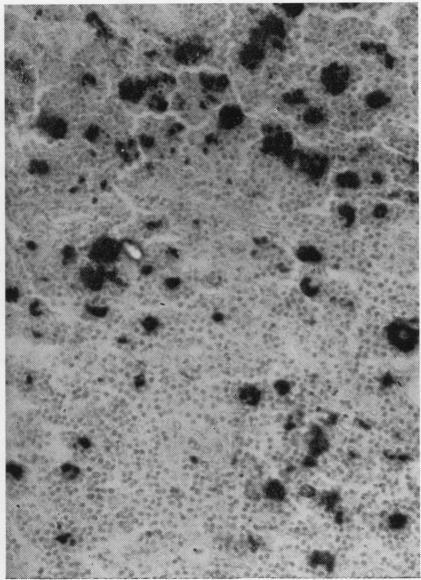

The clinical course and pathological features of four cases of Waldenström's macroglobulinaemia are described. One was associated with a localized carcinoma of the bronchus and one with a chromophobe adenoma of the pituitary. Trypsin digest preparations of the retina were examined in two cases, one with severe retinopathy and the other with no clinical evidence of ocular disease, and the findings are briefly described. The aetiology of the anaemia is discussed. Haemolysis due to circulating autoantibodies was not demonstrated in any of the cases. Erythrophagocytosis was a prominent feature in case 4, of moderate degree in cases 1 and 2, and inconspicuous in case 3. It was not proportionate to the serum macroglobulin levels. The cytological and histological features in all four cases are distinctive, and their value in differential diagnosis is stressed.

本文描述了4例华氏巨球蛋白血症的临床病程及病理特征。其中1例与支气管局部癌有关,1例与垂体嫌色性腺瘤有关。对2例患者的视网膜进行了胰蛋白酶消化制剂检查,1例有严重视网膜病变,另1例无眼部疾病的临床证据,并简要描述了检查结果。文中讨论了贫血的病因。所有病例均未证实存在由循环自身抗体导致的溶血现象。红细胞吞噬现象在病例4中较为突出,在病例1和2中程度中等,在病例3中不明显。其与血清巨球蛋白水平不成比例。所有4例的细胞学和组织学特征均有独特之处,并强调了它们在鉴别诊断中的价值。